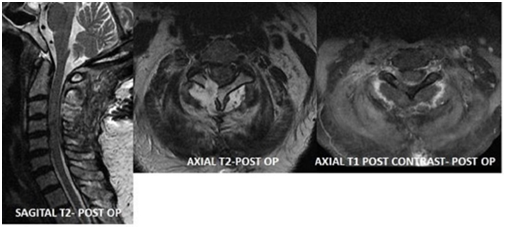

A 69 year old right handed female presents to ER with sudden onset right sided weakness. She had past medical history of diabetes mellitus, hypertension, hyperlipidemia and obesity. She developed right upper and lower extremity weakness which progressed by the time she presented to ER and she was unable to move her right side. She presented within 90 minutes and was initially examined by ER Physician within a minute of her presentation, stroke code (as per hospital's ischemic stroke guideline) was activated which lead to urgent CT Brain within 15 minutes and was examined by Neurologist within 30 minutes of her presentation. Quick history and collateral history, excluding the relative and absolute contraindications, neurologist noted she had right sided neck pain and had right sided hemiplegia. Neurologic examination at this stage showed she had flattened right naso-labial fold, right upper extremity power was 0/5 and right lower extremity was 0/5, without any sensory loss. She had absent reflexes all over and reduced tone and planters was extensor on the right and was flexor on the left side. Her NIHSS (National Institute of Health Stroke Scale) was 9. As initial CT brain was unremarkable, her family was consented for Fibrinolytic therapy with IV rtPA (recombinant tissue Plasminogen Activator) and was dispensed at a dose of 0.9mg/kg within 45 minutes of her presentation. While in the transit from ER to Stroke Unit that is within 3 hours post her IV rtPA, she started to complain that she can't feel her left leg and arm and has developed left sided weakness. This prompted a repeat CT brain which was unremarkable for any signs of hemorrhage and or ischemia. Re-examination at this stage showed she had quadraparesis, with dense right hemiplegia of power 0/5 in the right upper and lower extremity and also left hemiparesis with power 1/5 in the left lower extremity and 2/5 in the left upper extremity with reduced tone all over and absent reflexes. Her Babinski's response was extensor on the right side and was unequivocal on the left side. She also had left hemi-sensory loss to pinprick and temperature sense up to her neck sparing the face along with right horner's (ptosis, smaller pupil and enopthalmos) with preserved extra ocular movements. Her neck pain had worsened and has been requiring opioid analgesics, with new development of her symptoms and signs this lead to further neuroimaging in the form of MRI Brain Stroke Protocol which was unremarkable and MRI Cervical spine which showed spindle-shaped extradural lesion extending from C2 to C6 exerting significant mass effect on the thecal sac and related spinal cord with subsequent cord edema. The lesion predominantly is of low signal in T2 and intermediate signal in T1 displaying tiny foci of enhancement after administration of contrast, suggesting underlying tumor with a surrounding hematoma, Figure 1. Emergent neurosurgical evaluation prompted urgent cervical decompression in the form of right hemi-laminectomy from C2 to C5 which revealed extra-dural tumor with clotted hematoma which was sub- acute, compressing the spinal cord this was excised, Figure 2, and with resultant improvement in her left sided motor function, she remained weak on the right side and has been treated with IV dexamethasone and with aggressive physiotherapy. This case highlights usual presentation with a rarest reason mimicking stroke.

Figure 2 Post-Operative; MRI of Cervical Spine with and without contrast showed status-post right hemi-laminectomy with successful evacuation of intra-spinal extradural mass lesion. Fluid signal seen in right postero-lateral aspect of spine likely due to postoperative changes.